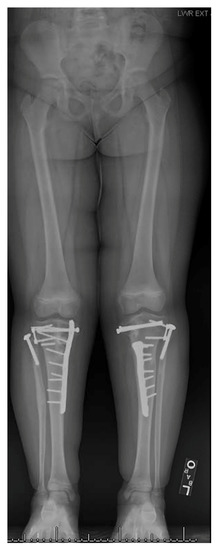

13. Osteotomies with Acute Correction

15. Combined Osteotomies